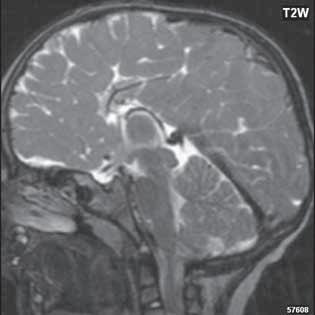

Roztroušená skleróza (RS) 189

II 1 1